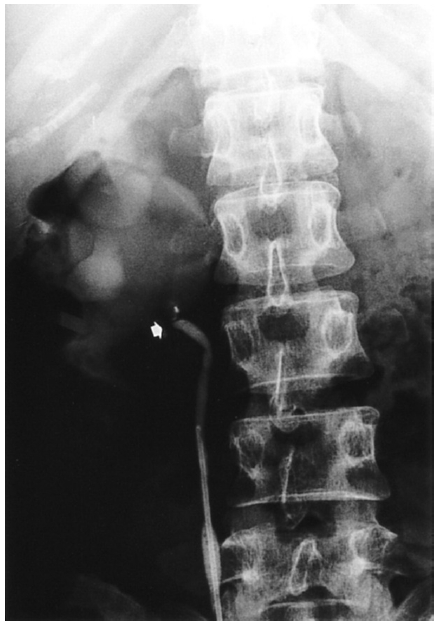

Kidney ultrasonogram showed a marked dilatation of the right pelvocalyceal system and right proximal ureter. However, the left kidney showed normal appearance. Excretory urogram revealed a marked right hydronephrosis with dilated calyces due to ureteropelvic junction obstruction (Figure 1). Computed tomography angiogram (CTA) clearly displayed the aberrant renal artery which originated from the aorta below the normal right renal artery (Figure 2). A source image of magnetic resonance angiogram (MRA) also showed a severe hydronephrosis of the right kidney and smooth obstruction of the right ureteropelvic junction due to extrinsic compression by an aberrant renal artery which originated from the aorta, crossing anteriorly to the ureteropelvic junction (Figure 3). Retrograde pyelogram demonstrated linear indentation of the proximal ureter (Figure 4). Tc-99m DTPA renal scan revealed a markedly delayed excretion of the right kidney. After furosemide infusion, the delayed right kidney excretion was somewhat improved (Figure 5).

Figure 1.

Excretory urogram after 30 min. shows severe dilatation of the right pelvocalyceal system with cortical thinning and smooth obstruction of the right ureteropelvic junction.